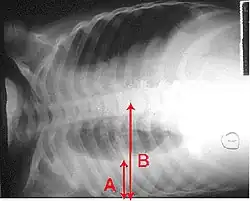

A pleural effusion appears as an area of whiteness on a standard posteroanterior chest X-ray.[15] Normally, the space between the visceral pleura and the parietal pleura cannot be seen. A pleural effusion infiltrates the space between these layers. Because the pleural effusion has a density similar to water, it can be seen on radiographs. Since the effusion has greater density than the rest of the lung, it gravitates towards the lower portions of the pleural cavity. The pleural effusion behaves according to basic fluid dynamics, conforming to the shape of pleural space, which is determined by the lung and chest wall. If the pleural space contains both air and fluid, then an air-fluid level that is horizontal will be present, instead of conforming to the lung space.[16] Chest radiographs in the lateral decubitus position (with the patient lying on the side of the pleural effusion) are more sensitive and can detect as little as 50 mL of fluid. Between 250 and 600mL of fluid must be present before upright chest X-rays can detect a pleural effusion (e.g., blunted costophrenic angles).[17]

Chest computed tomography is more accurate for diagnosis and may be obtained to better characterize the presence, size, and characteristics of a pleural effusion. Lung ultrasound, nearly as accurate as CT and more accurate than chest X-ray, is increasingly being used at the point of care to diagnose pleural effusions, with the advantage that it is a safe, dynamic, and repeatable imaging modality.[18] To increase diagnostic accuracy of detection of pleural effusion sonographically, markers such as boomerang and VIP signs can be utilized.[19]

-

Massive left-sided pleural effusion (whiteness) in a patient presenting with lung cancer. -

A pleural effusion as seen on lateral upright chest x-ray -

Pleural effusion as seen behind the heart.[20]